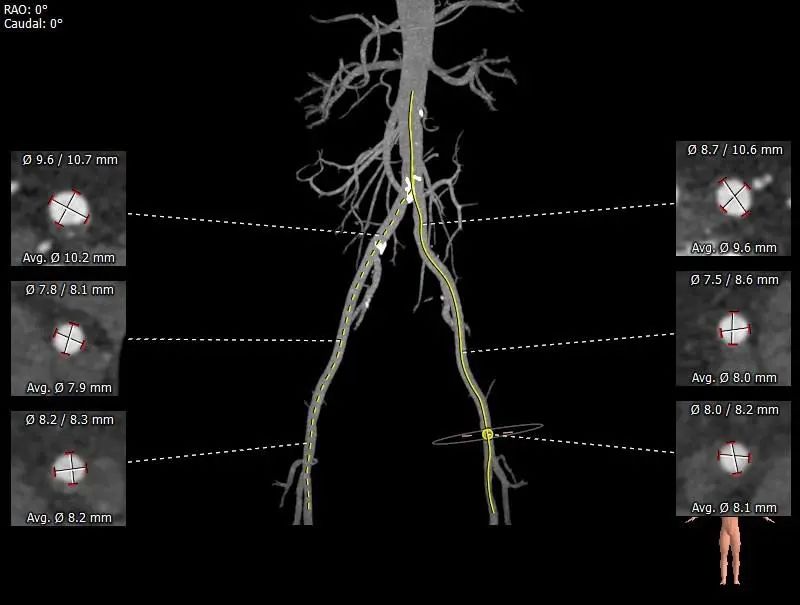

双侧髂动脉未见明显扭曲,股动脉穿刺区域未见钙化斑块,入路血管直径良好。

外周血管及主动脉弓解剖